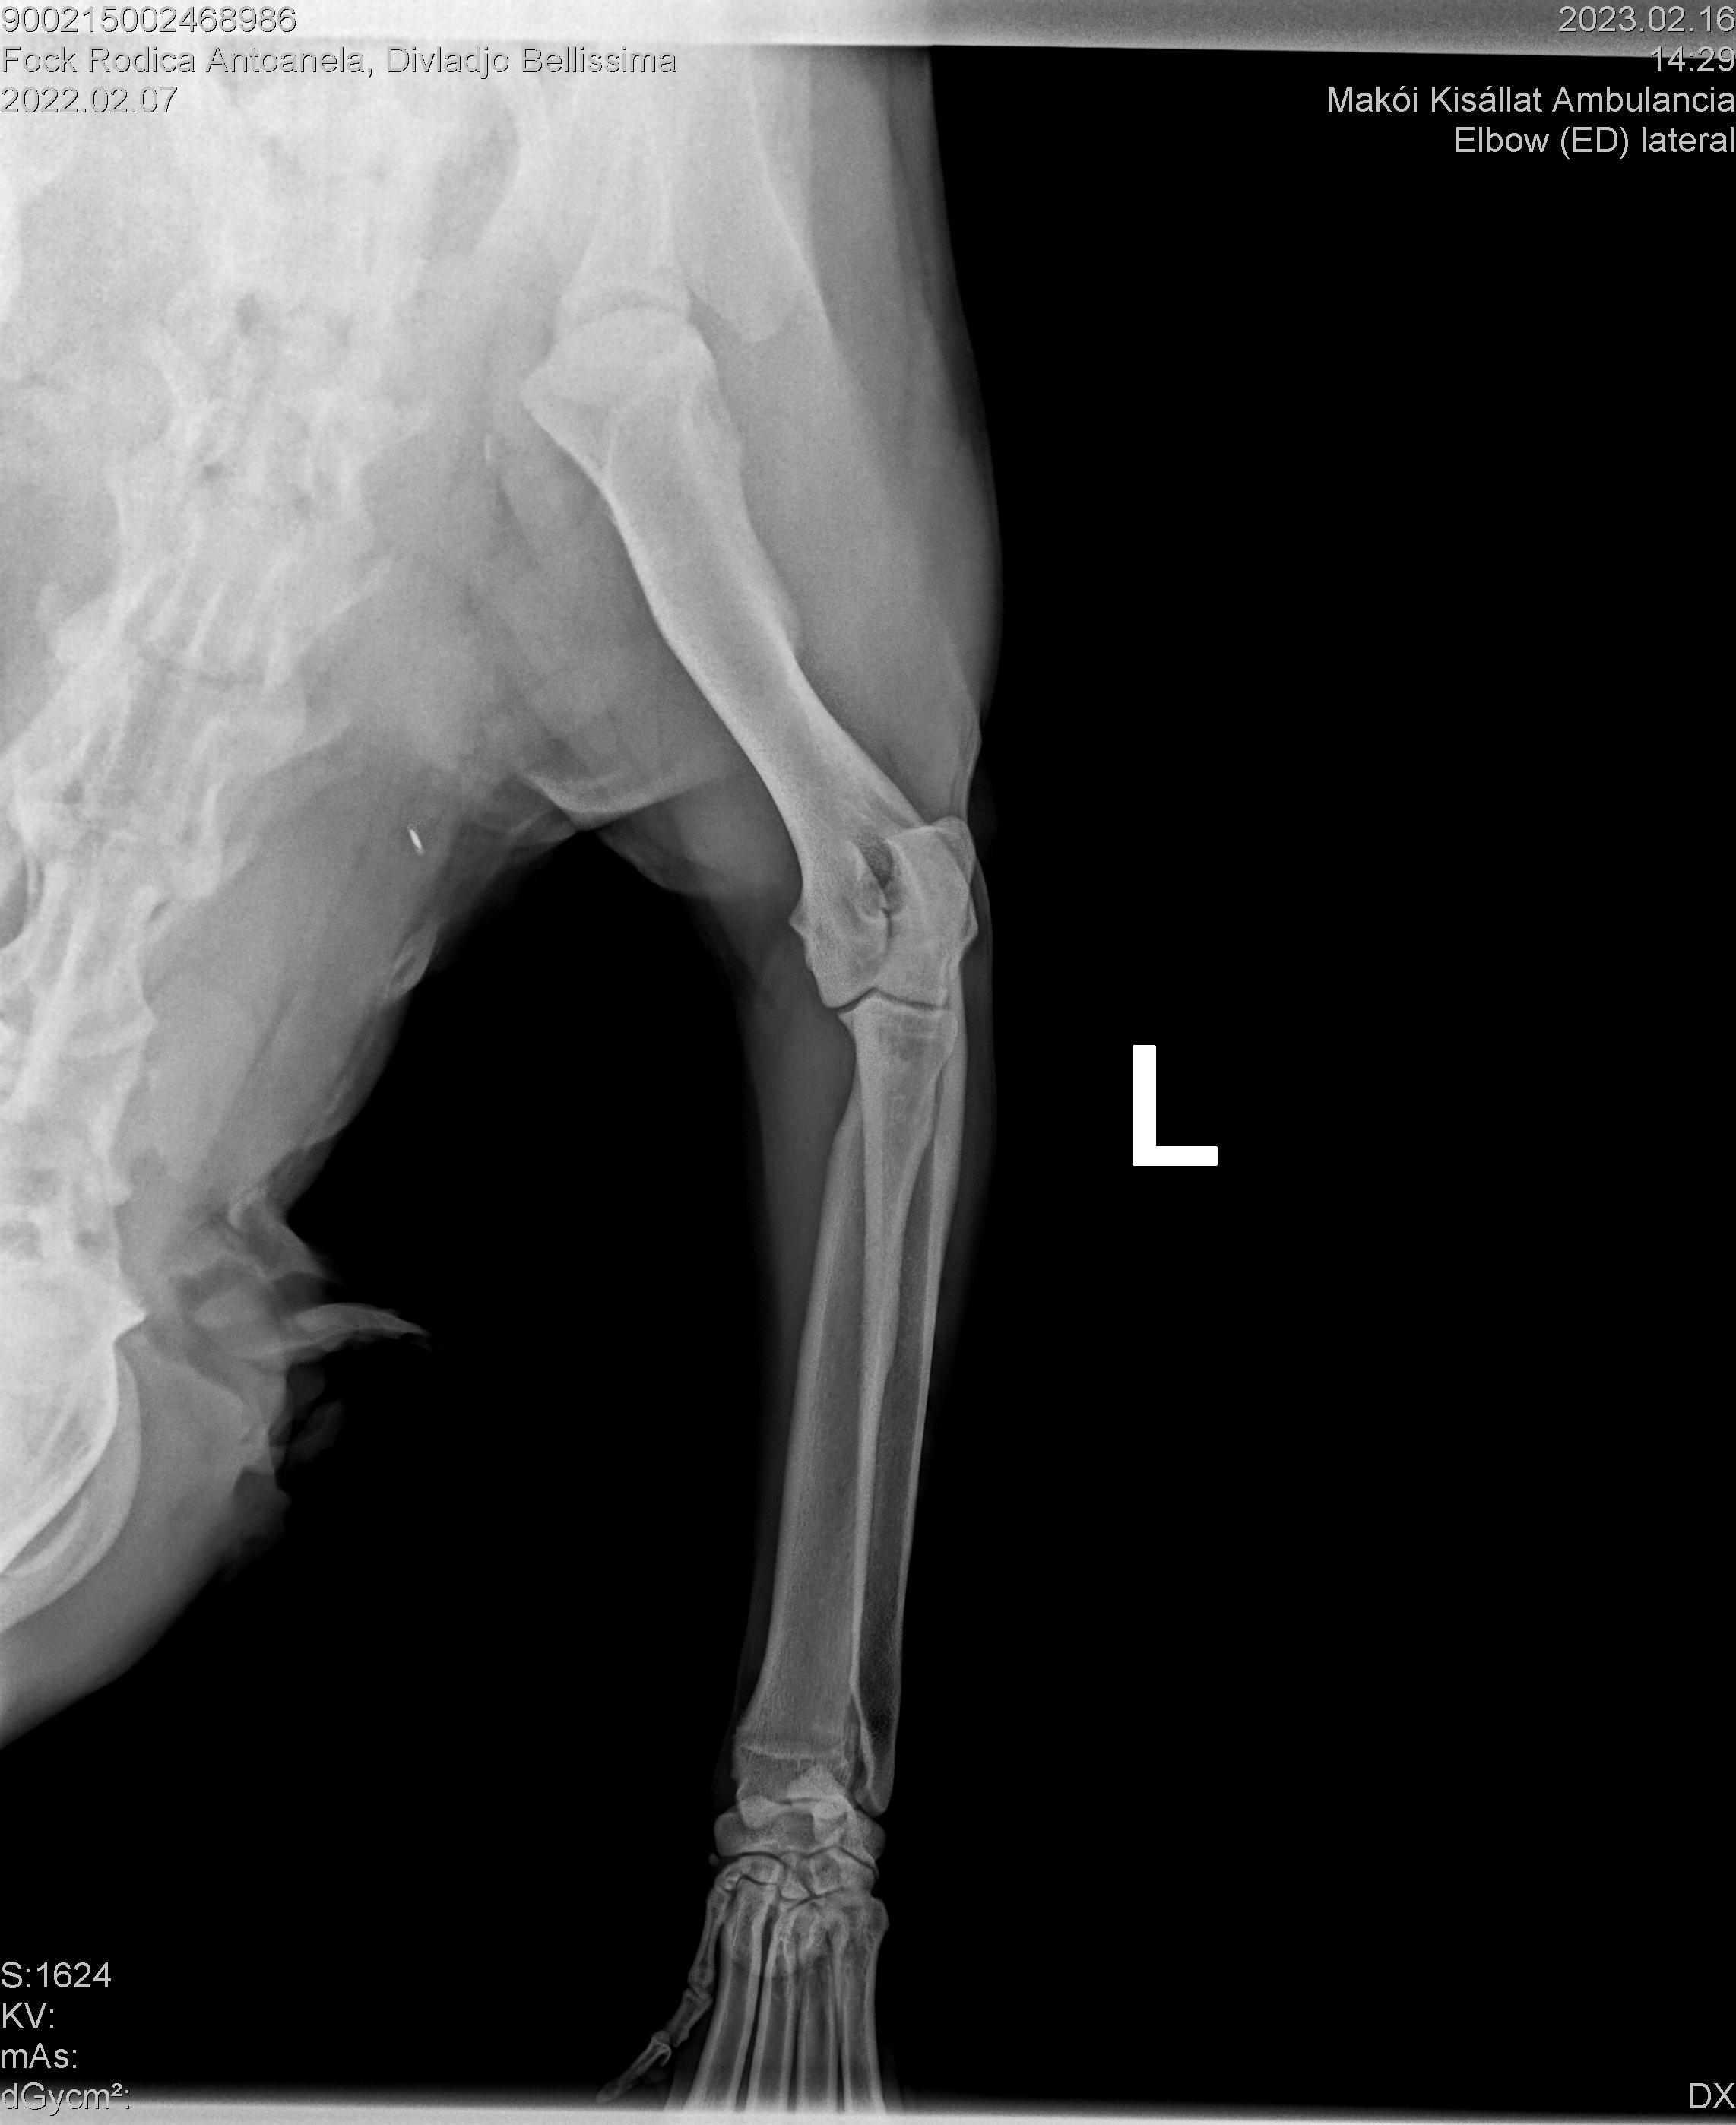

DIVLADJO BELLISSIMA

( BELLISSIMA )

Data nasterii:

07.02.2022